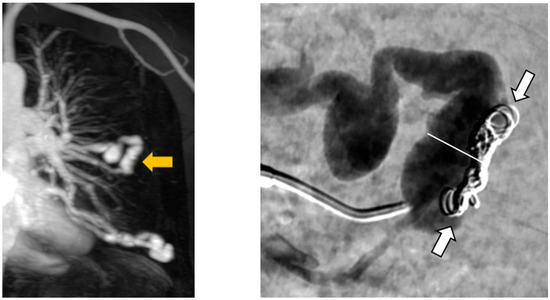

Furthermore, angiography images were examined for possible causes of reperfusion during re-embolization. In a total of 64 recanalized AV shunts, recanalization could be attributed to inadequate packing density of the implanted coils in 52 feeding arteries. Two examples are shown in Figure 7. In 15 of the 52 recanalized feeding arteries, we can further see a positioning of the embolization material on the wall of the vessel but not in the center (Figure 8).

The perfusion of PAVM was observed in two externally embolized malformations, which were initially embolized by detachable coils in the aneurysm sac. In another patient, reperfusion could be attributed to an increase in the size of the feeding artery. During the initial embolization at the age of four years, the diameter was 1.5 mm and seven years later a diameter of 2.1 mm was determined during re-embolization. In another patient, the dilatation of the feeding artery in the area of the implanted embolization material was observed. This was already seen in the MRA performed and confirmed in a subsequent angiography. Furthermore, the fixation of the implanted coils in the arterial wall was evident in the DSA series. Figure 9 shows both the screening and the angiography images, with the open arrow in the MRA image showing the dilation of the feeding artery and the white arrows in the DSA image indicating the fixation of the implanted coils. The white line also emphasizes the dilatation of the feeding artery. It should also be emphasized that the embolization material completely filled the feeding artery during initial therapy and that the complete occlusion of the vessel was achieved.

Figure 7. Presentation of two PAVM with insufficient packing density of implanted coils.

Figure 9. MRA shows a dilatation of the feeding artery at the implantation site (left) and confirmation by an implemented DSA (right).